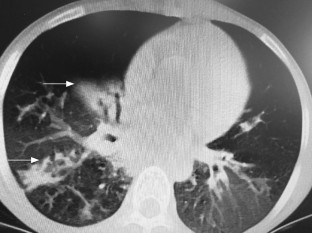

Fig. 1